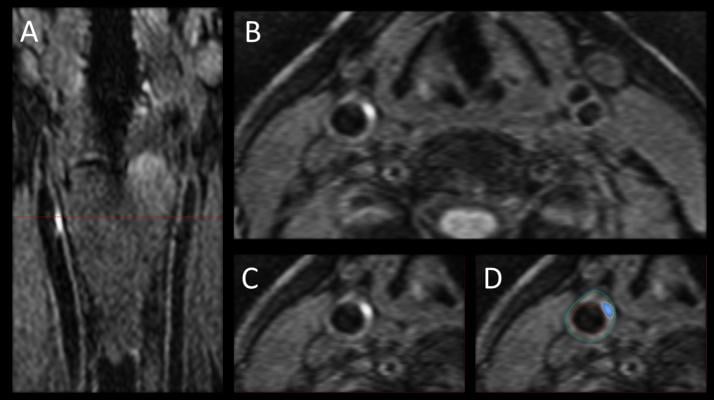

Image A shows the 3-D MRI intraplaque hemorrhage (IPH) sequence as acquired in the coronal plane. The red dotted line indicates the level at which the reformatted axial plane, B, was obtained. C shows the section of the right carotid artery with a region of high signal consistent with IPH. Contours are drawn for the outer wall (green) and lumen (red) with the area of IPH in this segment shaded blue in D.

For the new study, researchers used 3-D MRI to study the carotid arteries for evidence of intraplaque hemorrhage (IPH), an indicator of advanced atherosclerotic disease.

Of the 159 patients imaged, 37, or 23.3 percent, had IPH in at least one carotid artery. Five of the 37 patients had IPH in both carotid arteries. IPH was found in the absence of carotid artery stenosis, or narrowing, and was associated with an increased carotid artery wall volume as measured by 3-D MRI.